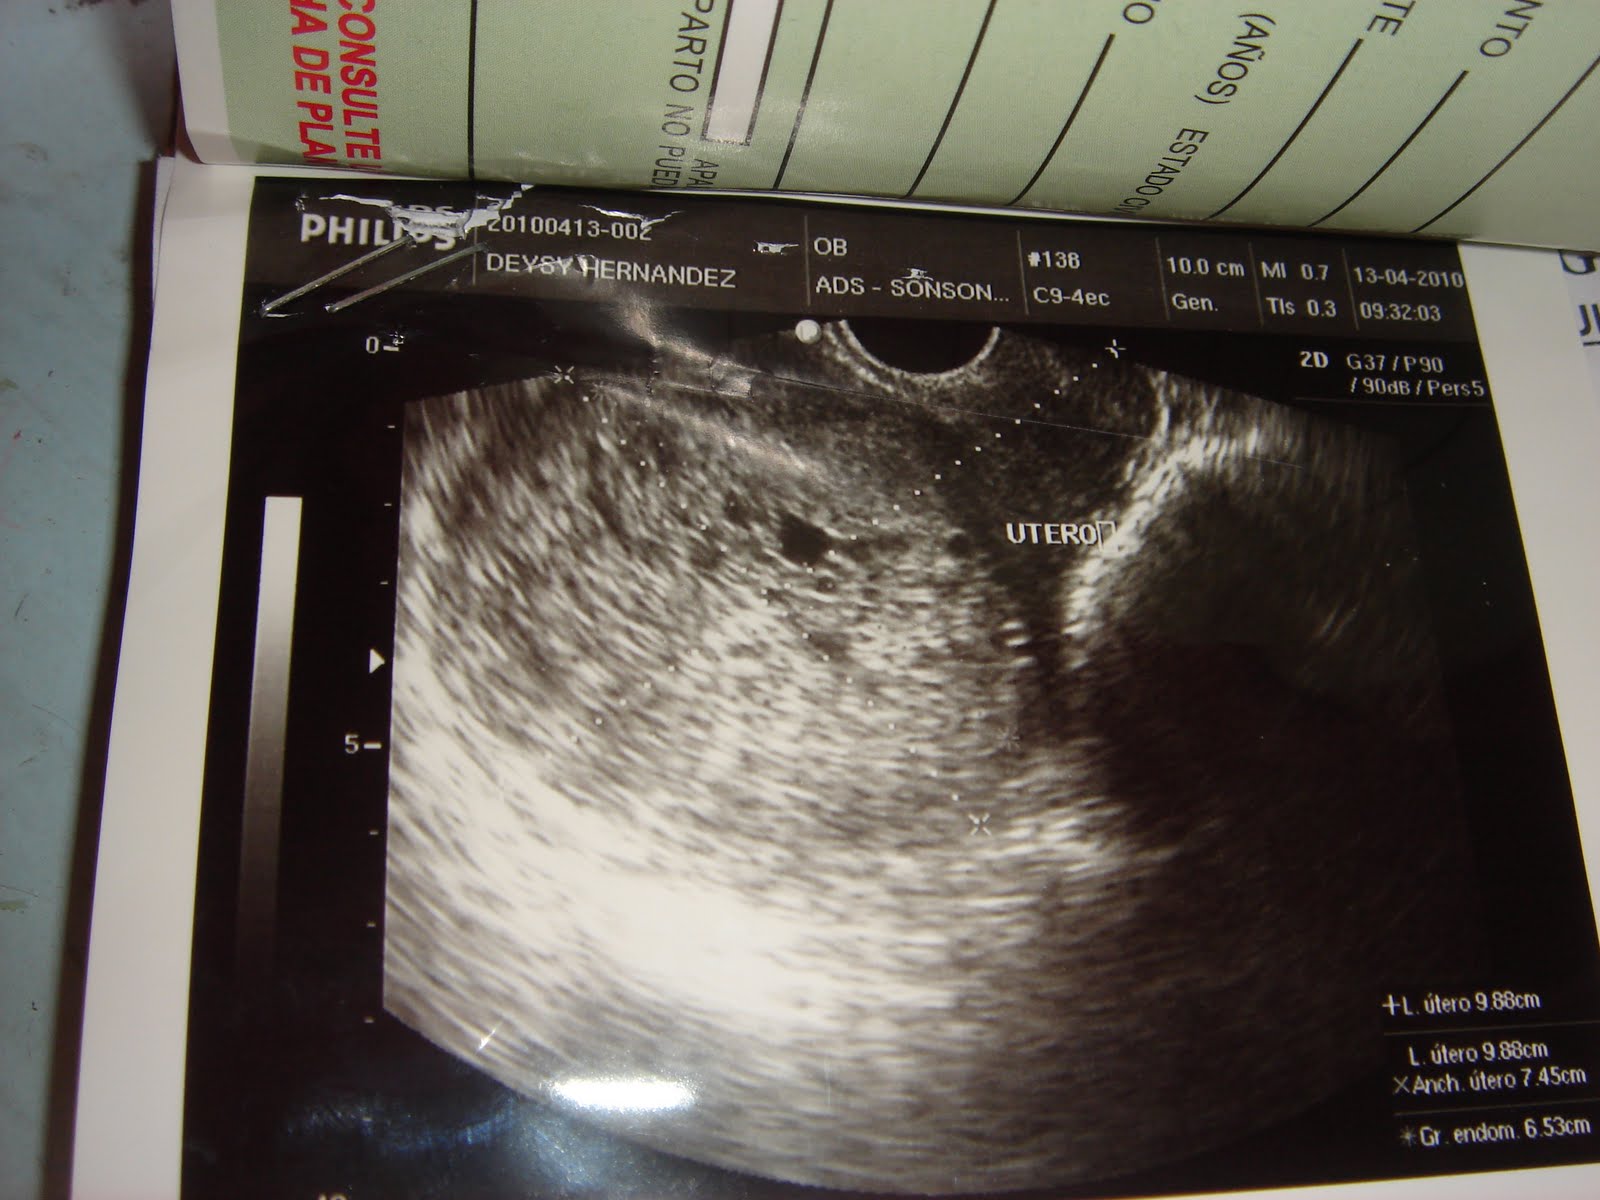

Throwing Glass Bottles: Snowstorm In El Salvador

Throwing Glass Bottles: Snowstorm in El Salvador throwingglassbottles.blogspot.com

snowstorm throwing molar indicative pregnancy hydatidiform ultrasound mole